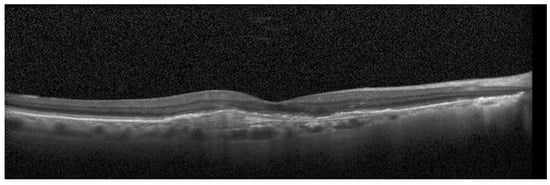

For the testing purpose and the presentation of the image manipulation detection method in the following section, the Optical Coherence Tomography (OCT) images, having the resolution of 1536 × 496 pixels, were used [33]. The OCT is a non-invasive imaging examination that uses light waves to take cross-section pictures of the human retina. One sample image of this type is shown in Figure 3. The tests show that the blocks: 37–39, 45–47, and 53–55, marked in Figure 4, should be usually selected for the process of inserting secret information. This conclusion is based on the analysis of spectra of diverse images with varying content and characteristics. For the selection of the best channel for watermark embedding, the mean of all absolute values from each block is calculated. The channel with the lowest mean is chosen as the first candidate for the subsequent data embedding operation. To increase the capacity of the watermark, other blocks can be selected afterward, considering their mean values sorted in ascending order.

Figure 3.

Sample OCT image.